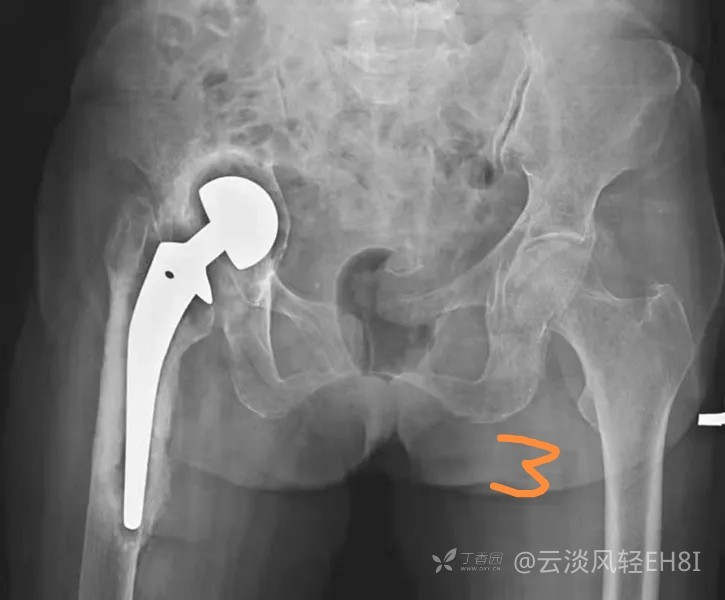

二、感染(图3)

人工髋关节置换术后感染是常见而又极其严重的并发症,感染经久不愈及扩大将导致死骨形成及假体松动。X线检查主要有以下几方面表现:①假体周围出现透亮带,透亮带轮廓不规则,宽窄不等,呈花边样,部分伴硬化边缘;②假体出现松动移位;③股骨柄髓腔内、外侧骨质破坏伴死骨及骨膜新生骨形成;④行造影时有腔道与关节相通。以上征象有时难以和无菌松动区别,结合临床上出现局部红肿热痛,可考虑深部感染的存在。